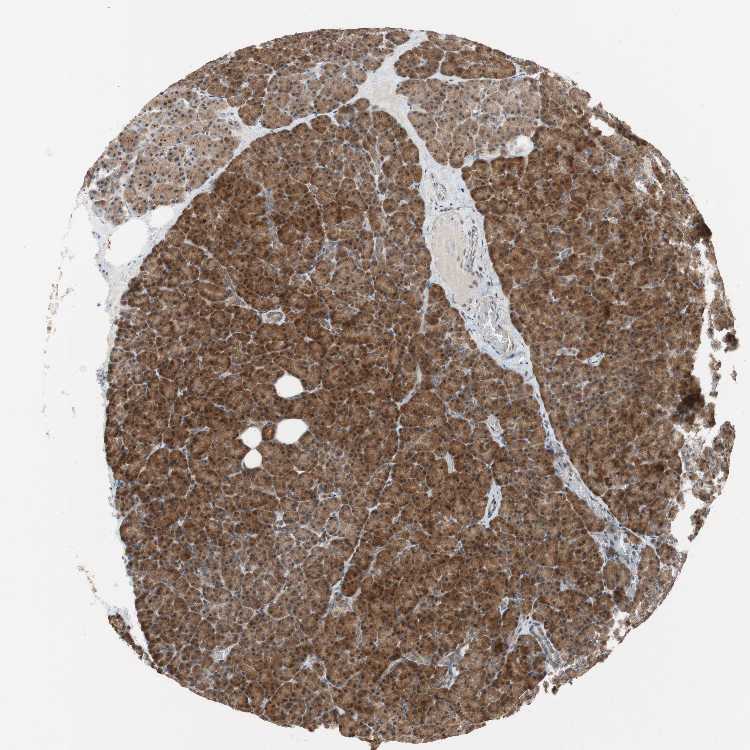

PANCREAS - Antibody stainingi

Antibody staining in the annotated cell types in the current human tissue is reported as not detected, low, medium, or high, based on conventional immunohistochemistry profiling in selected tissues. This score is based on the combination of the staining intensity and fraction of stained cells.

Each image is clickable and will lead to virtual microscopy that enables deeper exploration of all samples and also displays staining intensity scores, fraction scores and subcellular localization as well as patient and tissue information for each sample.

Antibody HPA004868Antibody HPA005729

Exocrine glandular cells MediumHigh

Pancreatic endocrine cells HighMedium